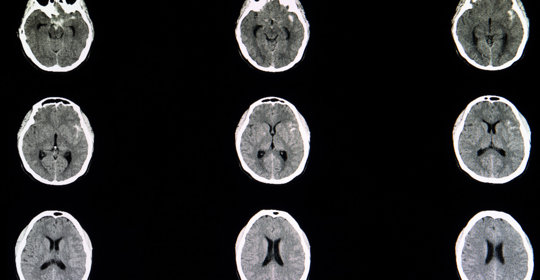

短暫性腦缺血發作的診斷與治療方法

創傷性腦損傷的診斷、治療與預防

毛毛樣腦血管病的診斷、治療及預防